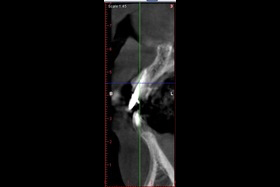

病患植牙前,拍攝3D立體斷層掃描。